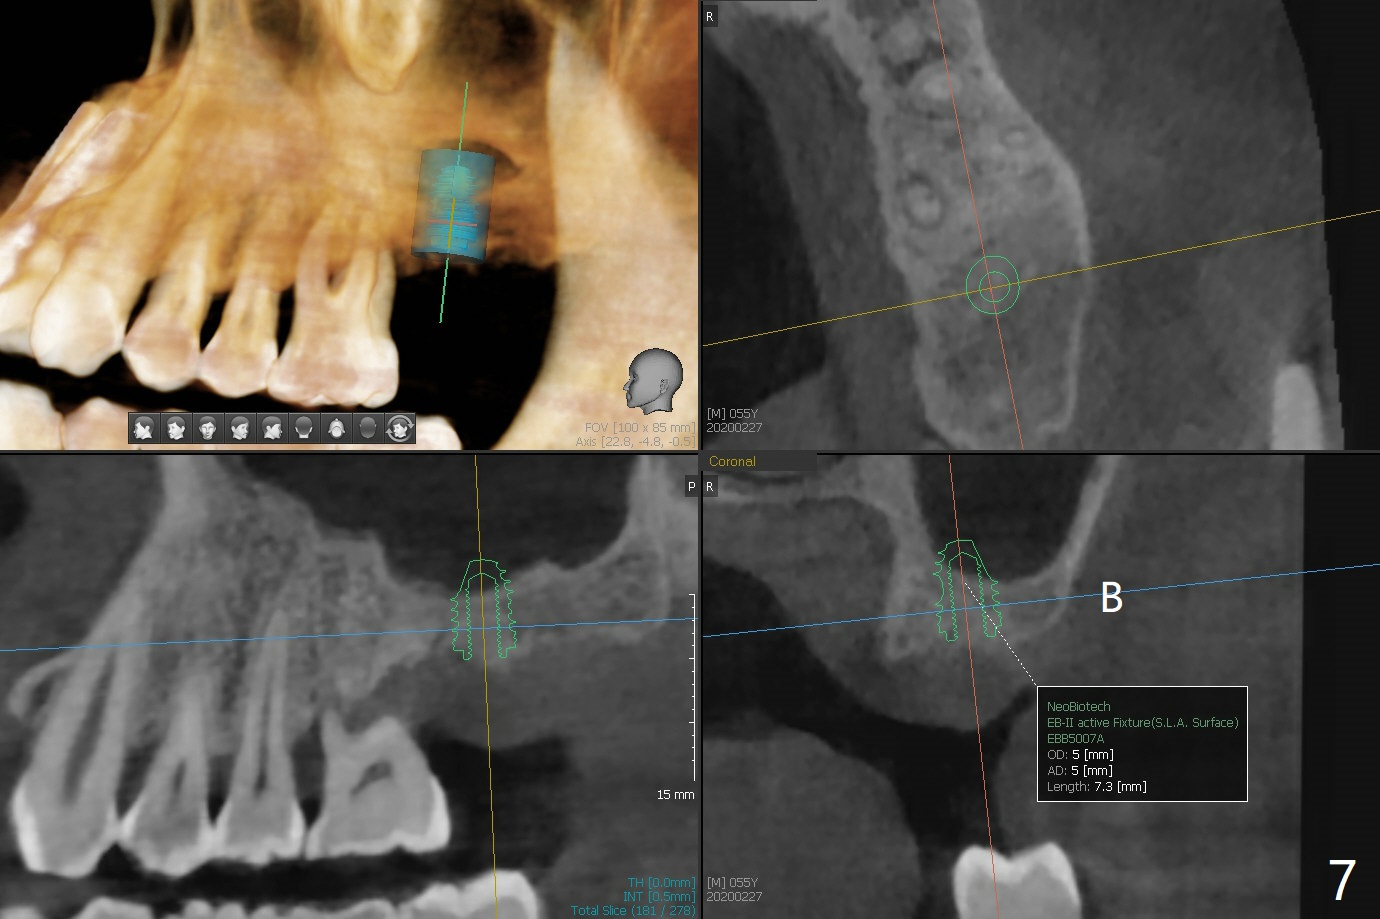

A 54-year-old man returns to clinic 5 months post SRP with chief complaint of UL loose tooth (#15, Fig.1). Since the remaining bone is limited after extraction, it is apparently unsuitable for immediate implant (Fig.2). Socket preservation seems to be able to gain bone height near gingival margin (Fig.3 red line). In fact 1 cc of cortical and cancellous bone mixture is used; after heavy debridement the bone graft is deposited on the distal root surface of the tooth #14 (Fig.4 arrow). The bone increases not only coronally, but also apically (Fig.5 blue lines, as compared to red lines denoting the original bone height). The bone reduces in height 10 months postop (Fig.6). Sinus lift is required for placement of a short implant (Fig.7). Socket preservation does not prevent post-extraction bone loss.